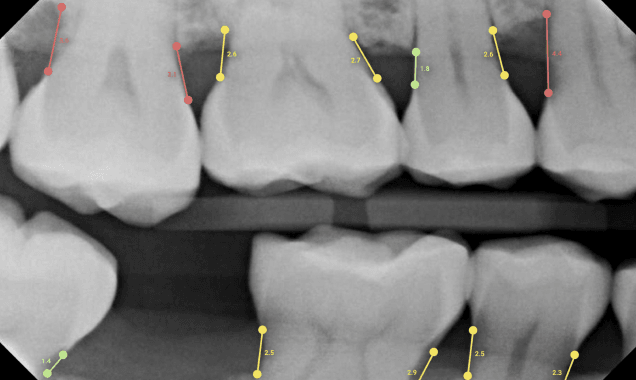

Enhanced Diagnostic Training AI tools help students identify dental conditions such as caries, bone loss, and periodontal disease directly on radiographic images. These real-time visual cues improve diagnostic accuracy and accelerate clinical skill development.

One of Overjet’s most powerful features is its diagnostic insight engine, which uses AI to analyze radiographs and highlight conditions such as caries, bone loss, and periodontal disease. This visual feedback helps students sharpen their diagnostic skills and understand clinical nuances more clearly and quickly.

What makes Overjet a powerful teaching tool is its commitment to explainable AI. Each diagnostic suggestion includes clear visual cues and annotations, helping students not only see the diagnosis but understand why it was made. This turns AI into a collaborative learning experience rather than a black-box solution.